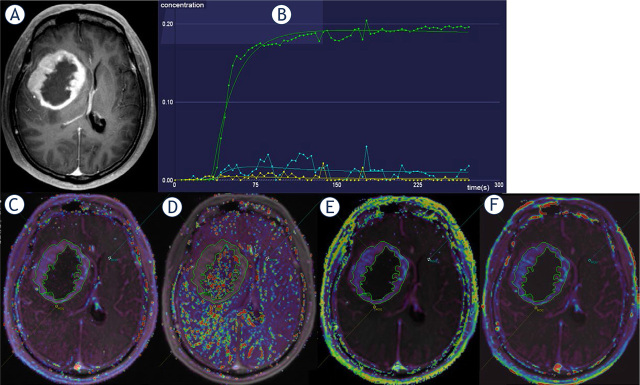

研究背景该研究旨在探讨影像学坏死(Imnecrosis)在胶质瘤分级中的诊断价值,预测胶质瘤的基因型和预后,并通过动态对比增强磁共振灌注成像(DCE-MRI)进一步评估肿瘤坏死:我们回顾性地纳入了150例经病理证实为成人弥漫性胶质瘤的患者(104例男性,平均年龄46岁),所有诊断均基于2021年世界卫生组织(WHO)中枢神经系统(CNS)分类。收集了病理坏死(Panecrosis)和基因突变信息。所有患者均接受了常规和 DCE-MRI 检查,并一直随访至 2021 年 5 月 31 日。Imnecrosis由两名经验丰富的神经放射科医生确定。DCE-MRI得出的指标图经过后处理,记录了肿瘤实质、瘤周和对侧区域每个指标的平均值:在定义瘤体坏死时,观察者之间的一致性很高(Kappa = 0.668,p < 0.001),瘤体坏死和泛坏死之间的一致性也很高(Kappa = 0.767,p < 0.001)。与低级别胶质瘤相比,高级别胶质瘤有更多的Imnecrosis(85.37%,P<0.001),并且Imnecrosis随着胶质瘤级别的增加而显著增加。IDH-野生型、1p19q-非缺码和CDKN2A/B-杂合子缺失胶质瘤中的Imnecrosis明显增多。通过多变量考克斯回归分析,脑坏死是胶质瘤的一个独立且不利的预后因素(危险比=2.113,p=0.046)。此外,DCE-MRI得出的肿瘤实质中血管外细胞外体积分数(ve)在鉴别Panecrosis和Imnecrosis方面显示出最高的诊断效率,特异性很高(分别为83.3%和91.9%):结论:Imnecrosis可为胶质瘤的分级、基因型和预后预测提供Panecrosis之外的补充证据,而肿瘤实质中的ve可帮助预测肿瘤坏死,且特异性高。

Background: The aim of the study was to investigate the diagnostic value of imaging necrosis (Imnecrosis) in grading, predict the genotype and prognosis of gliomas, and further assess tumor necrosis by dynamic contrast-enhanced MR perfusion imaging (DCE-MRI).

Patients and methods: We retrospectively included 150 patients (104 males, mean age: 46 years old) pathologically proved as adult diffuse gliomas and all diagnosis was based on the 2021 WHO central nervous system (CNS) classification. The pathological necrosis (Panecrosis) and gene mutation information were collected. All patients underwent conventional and DCE-MRI examinations and had been followed until May 31, 2021. The Imnecrosis was determined by two experienced neuroradiologists. DCE-MRI derived metric maps have been post-processed, and the mean value of each metric in the tumor parenchyma, peritumoral and contralateral area were recorded.

Results: There was a strong degree of inter-observer agreement in defining Imnecrosis (Kappa = 0.668, p < 0.001) and a strong degree of agreement between Imnecrosis and Panecrosis (Kappa = 0.767, p < 0.001). Compared to low-grade gliomas, high-grade gliomas had more Imnecrosis (85.37%, p < 0.001), and Imnecrosis significantly increased with the grade of gliomas increasing. And Imnecrosis was significantly more identified in IDH-wildtype, 1p19q-non-codeletion, and CDKN2A/B-homozygous-deletion gliomas. Using multivariate Cox regression analysis, Imnecrosis was an independent and unfavorable prognosis factor (Hazard Ratio = 2.113, p = 0.046) in gliomas. Additionally, extravascular extracellular volume fraction (ve) in tumor parenchyma derived from DCE-MRI demonstrated the highest diagnostic efficiency in identifying Panecrosis and Imnecrosis with high specificity (83.3% and 91.9%, respectively).

Conclusions: Imnecrosis can provide supplementary evidence beyond Panecrosis in grading, predicting the genotype and prognosis of gliomas, and ve in tumor parenchyma can help to predict tumor necrosis with high specificity.